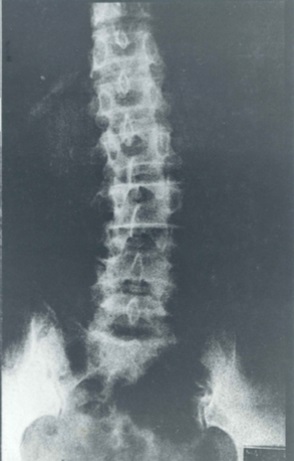

カネミ油症発生から46年を経過し、骨の痛み、変型、歩行困難等を訴える被害者が多い。

2013年6月29日撮影。50代の男性。現在の被害者(一昨年まで未認定者)。クロルアクネ、色素沈着、歯の折れ、骨の病気が続いた。現在はがんを発症。